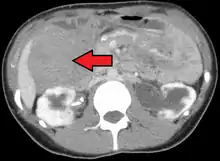

| Desmoid tumor as seen on CT scan | |